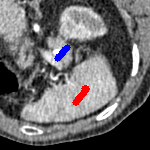

The motivation for this work comes from observing contradictions in using piecewise-constant intensity fitting terms in selective segmentation. Whilst good results are possible with this approach, the exceptional cases lead to severe limitations in practice. This is quite common in medical imaging as demonstrated in Fig. 1, where the target foreground has a low intensity. Given that the corresponding background includes large regions of low intensity, the optimal average intensities for this segmentation problem are and . For cases where , we see that by (1), almost everywhere in the domain . This means that it is very difficult to achieve an adequate result, without an over-reliance on the user input or parameter selection.

3 Alternative Selective Segmentation Models

We now introduce two recent methods that incorporate user input to perform selective segmentation. Each involves input in the form of foreground/background regions to indicate relevant structures of interest. An example of this can be seen in Fig. 18, where red regions indicate foreground and blue regions indicate background. We compare against the work of Nguyen et al. Nguyen:12 , which uses a similar convex relaxation framework to the proposed approach, and Dong et al. SRW , which uses a variation of the random walk approach. We summarise the essential aspects of each approach in the following.

for and as defined in (33). This is consistent with respect to the intensities of the observed object and the concept of selective segmentation. In Fig. 3 we see the difference between CV and the proposed fitting terms for given user input on a CT image. For the CT image, the CV fitting terms are near 0 within the target region. This is despite there being a distinct homogeneous area with good contrast on the boundary. This illustrates the problem we are aiming to overcome. With the proposed fitting term this phenomenon should be avoided in cases like this. By defining as in (33) there is no contradiction if the foreground and background intensities of the target region are similar.